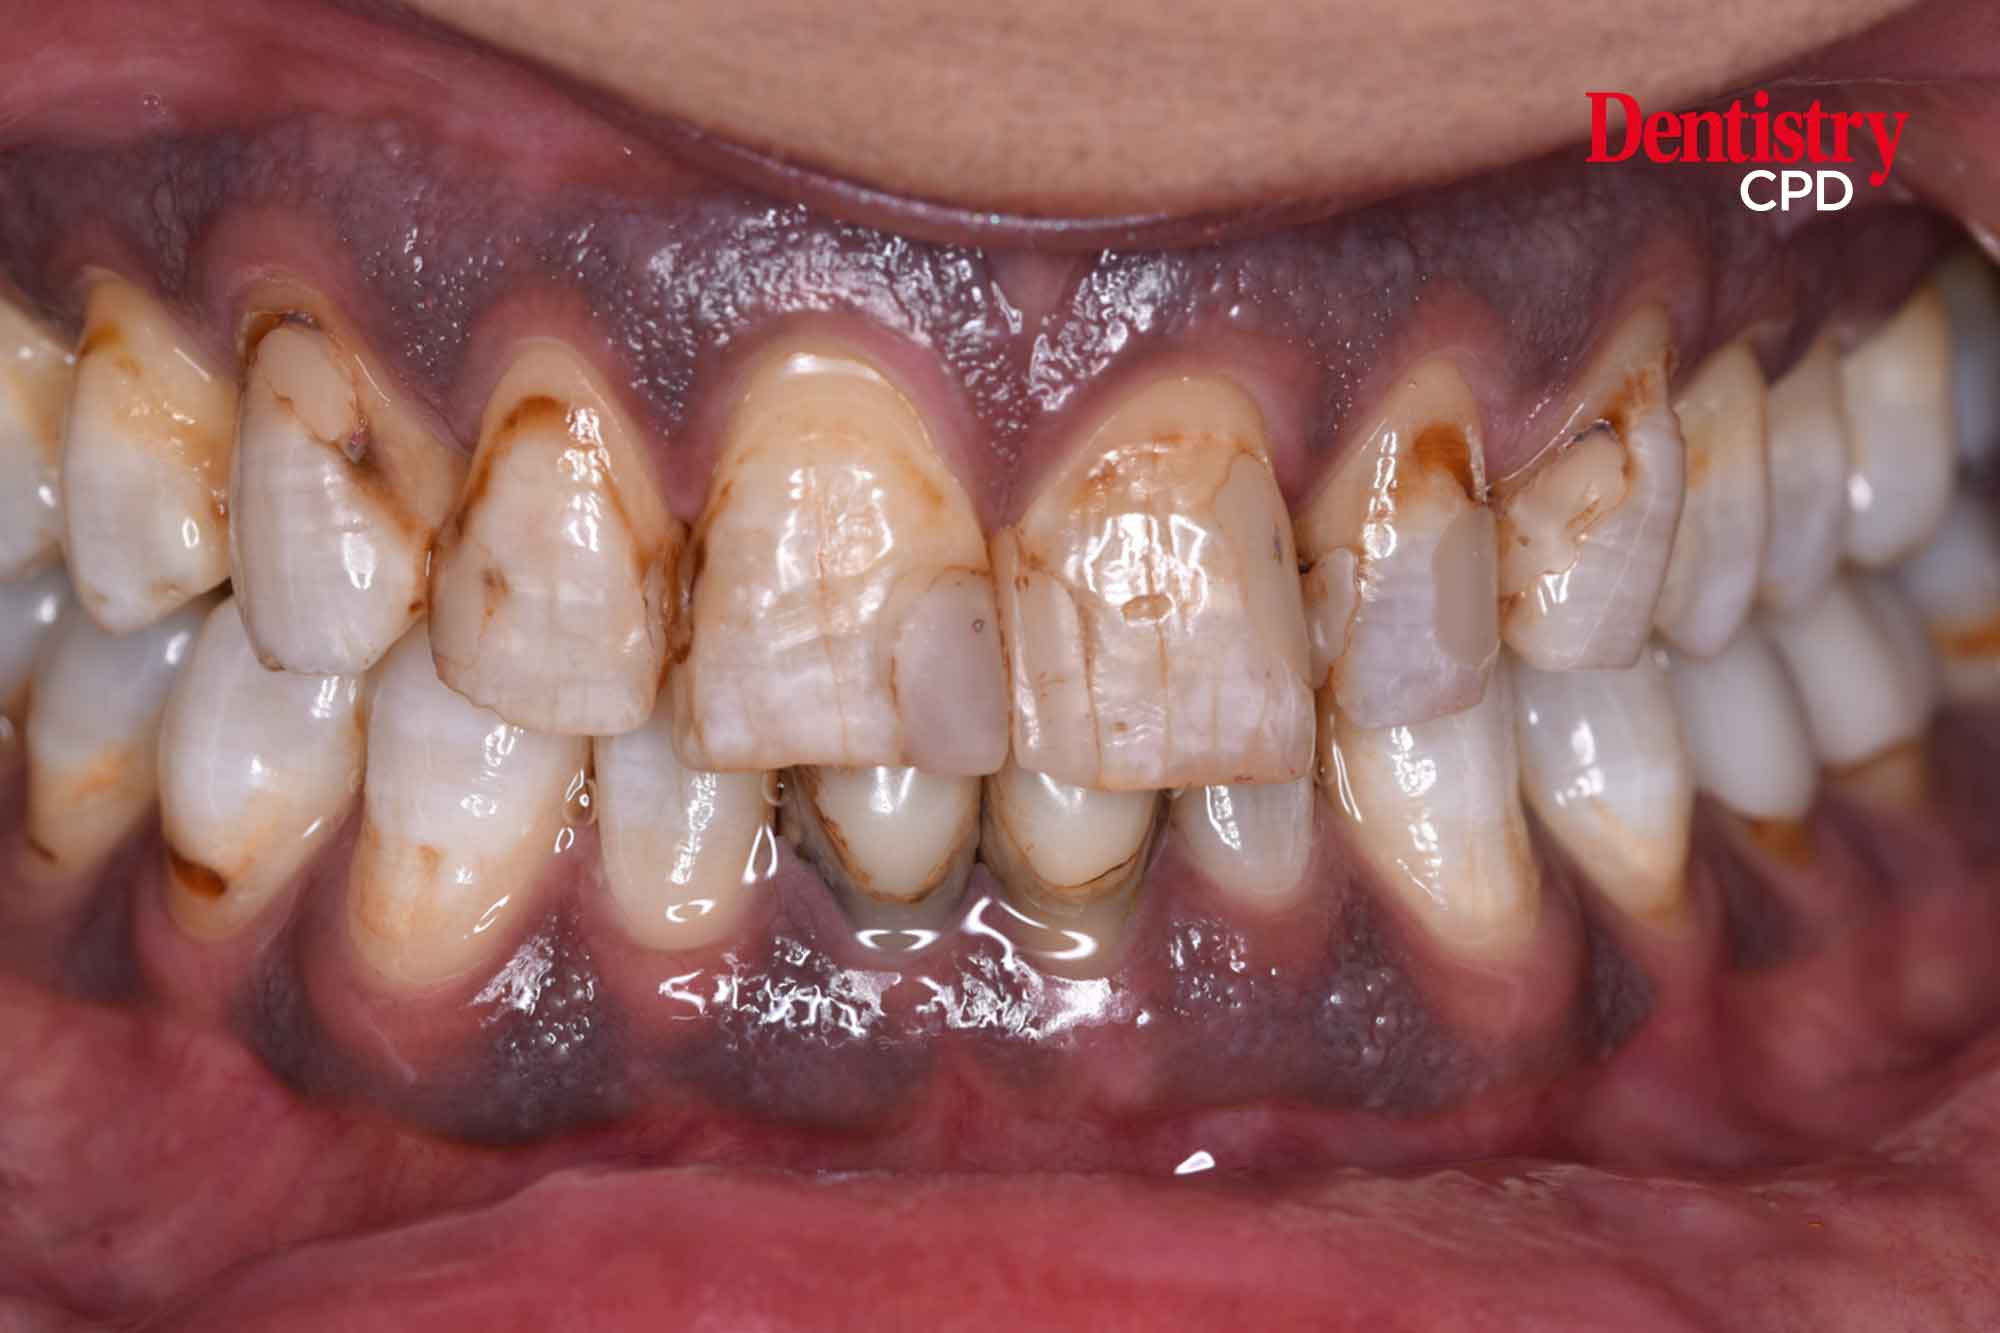

Management of stained fluorotic teeth

To explore the management of severe fluorosis by combined minimal invasive aesthetic procedure.